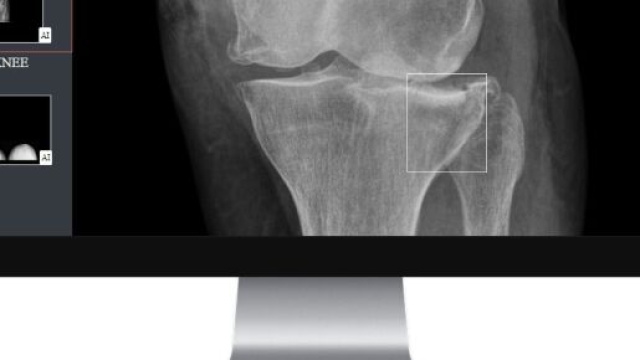

Gleamer a développé BoneView, le premier logiciel qui assiste les radiologues en traumatologie grâce à un diagnostic semi-automatisé. Comment cela est-il né ?

La radiographie traumatique est un examen chronophage, difficile à interpréter, et pour lequel les radiologues sont en nombre insuffisants. Dans les hôpitaux publics français par exemple, 3 radiographies sur 4 sont interprétées en première instance par un médecin urgentiste, et non un radiologue, faute de moyens.

Nous sommes convaincus que l’IA a un rôle à jouer pour épauler les établissements de santé qui rencontrent des difficultés d’organisation dans l’interprétation de ces examens.